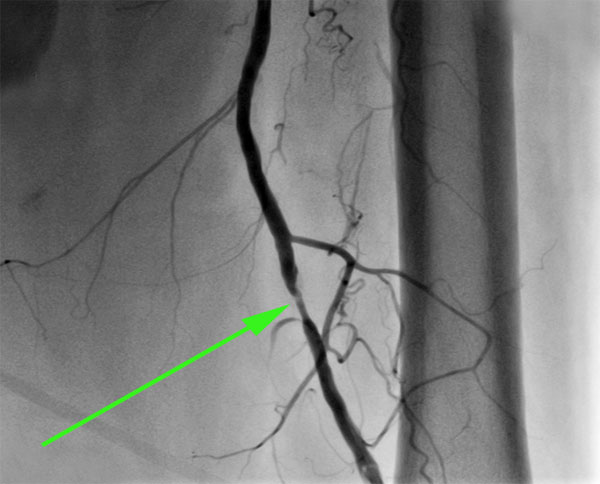

Изображения, связанные с атеросклерозом нижних конечностей и его лечением